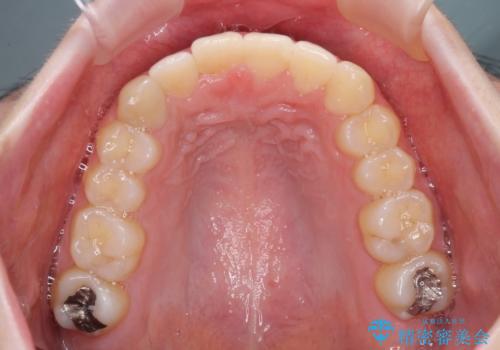

- 口の閉じにくさと割れてしまった奥歯を気にして来院された患者様です。

IPR(歯と歯の間を削る)と歯列全体の後方移動によって口元が引っ込むように設計し、インビザラインにより治療を行うこととしました。

割れてしまった奥歯は抜歯し、矯正治療中の良いタイミングでインプラントを埋入することとしました。

インプラントは、治療期間を短くすることが可能な、ストローマン社のSLActiveを使用することとしました。

上下正中がずれていたため、抜歯による矯正治療も検討しましたが、口元がそれほど突出していなかったため、非抜歯にて矯正することになりました。

その結果正中のズレは残りましたが、口を閉じたときの感覚や奥歯の咬み合わせには全く問題なく、患者様には大変満足していただきました。